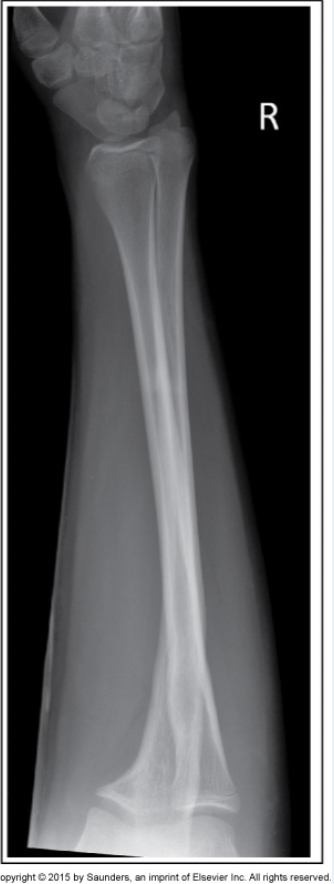

46

What type of fracture is evident? a.Smith’s fracture b.Stress fracture c.Greenstick fracture d.Colles’ fracture

d.Colles’ fracture

47

When placing the IR beside the patient for a cross table lateral hip image (axiolateral projection), the IR is required to be: a.parallel with the femoral neck b.parallel with the femoral shaft c.perpendicular with the femoral shaft d.perpendicular with the femoral neck

a.parallel with the femoral neck

48

Which image will provide the most amount of information for a suspected medial tibial plateau fracture? a.Lateral knee b.AP knee c.Internal rotation oblique knee d.External rotation oblique knee

d.External rotation oblique knee

49

Which of the following would best demonstrate calcaneal spurs? a.Lateral view of the ankle b.Internal rotation oblique of the ankle c.Medial rotation oblique of the foot d.Lateral view of the foot

d.Lateral view of the foot

50

Which positioning maneuver should be performed to place the femoral necks parallel with the IR for an AP projection of the pelvis? a.Rotate the lower limbs medially 15 to 20 degrees. b.Flex the hips and abduct the femora laterally 15 to 20 degrees. c.Rotate the lower limbs laterally 15 to 20 degrees. d.This image is acceptable due to the obvious femoral neck fracture

a.Rotate the lower limbs medially 15 to 20 degrees

51